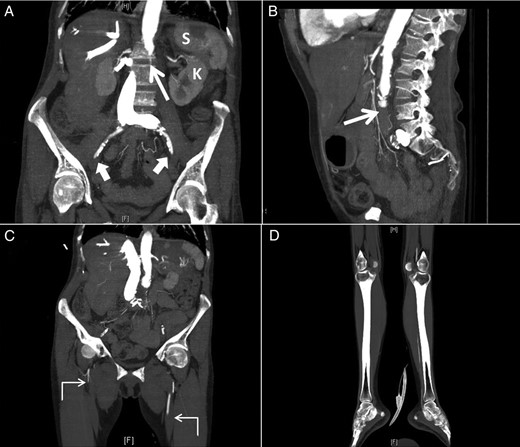

On further examination, her legs were cold and mottled and a CT angiography of the abdomen, pelvis and both lower extremities revealed occlusion of the distal infra-renal abdominal aorta and iliacs (Fig. 2A and B) and superficial femoral arteries with weak runoff on the left and no runoff on the right side (Fig. 2C and D). Multifocal infarcts of the spleen and both kidneys were also noticed (Fig. 2A).

Sagittal (A) and coronal (B) computed tomographic angiogram images of the abdomen and pelvis and coronal images (C and D) of both lower extremities showing occlusion of the distal infra-renal abdominal aorta (thin arrow) and iliacs (thick arrows) and superficial femoral arteries with weak runoff on the left and no runoff on the right side (angled arrows) with multifocal infarcts of the spleen (S) and left kidney (K).